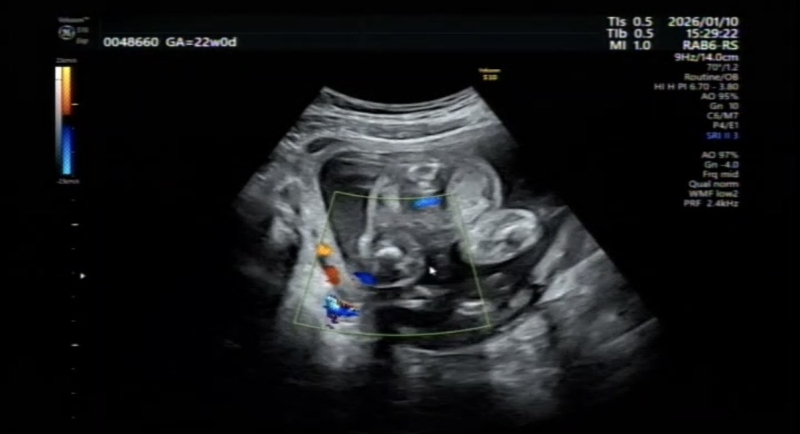

掲載いただきましたお写真を拝見しましたが、こちらの画像は血管を診るためのエコーになっていて、ちょうど見たい外陰部のところがよく見えない状態になっています。

陰部のところには、ちょうど臍の緒がかかってしまっていて、よく外陰部が見えない状態です。このお写真ですと、見たいところが見えない状態なので、性別がはっきりとは分かりません。